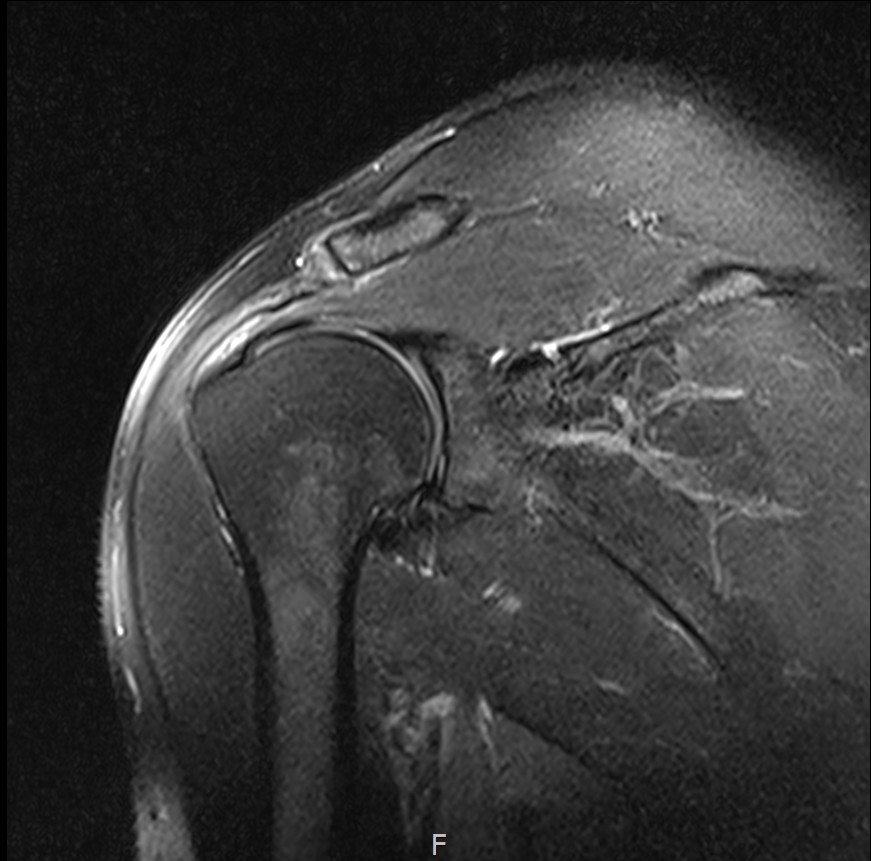

MRI를 검토해보았습니다.

회전근개 극상건의 점액낭면측(bursal-side) 부분파열. 처음보다 파열 범위가 약간 넓어져 있었고, 인대가 얇아진 소견도 보였습니다.

MRI: 극상건 점액낭면측 부분파열

인대 두께: 4.2mm (정상 5~6mm보다 얇음)